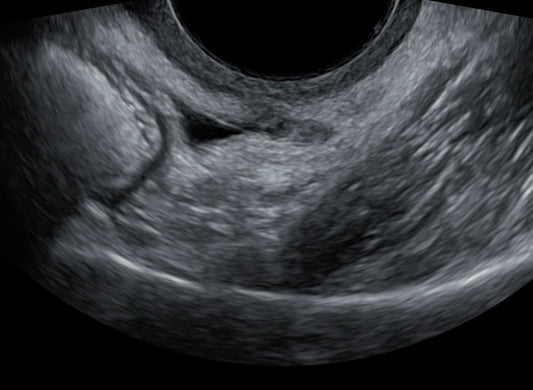

Understanding Endometriosis Diagnosis

As an experienced sonographer, I have witnessed the challenges that come with diagnosing endometriosis. This complex condition affects 1 in 7 women, leading to significant pain and complications. What is...